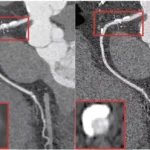

Clinical Implementation of PCCT In the last 5 years, more than 200 scientific articles have been written on photon-counting CT…